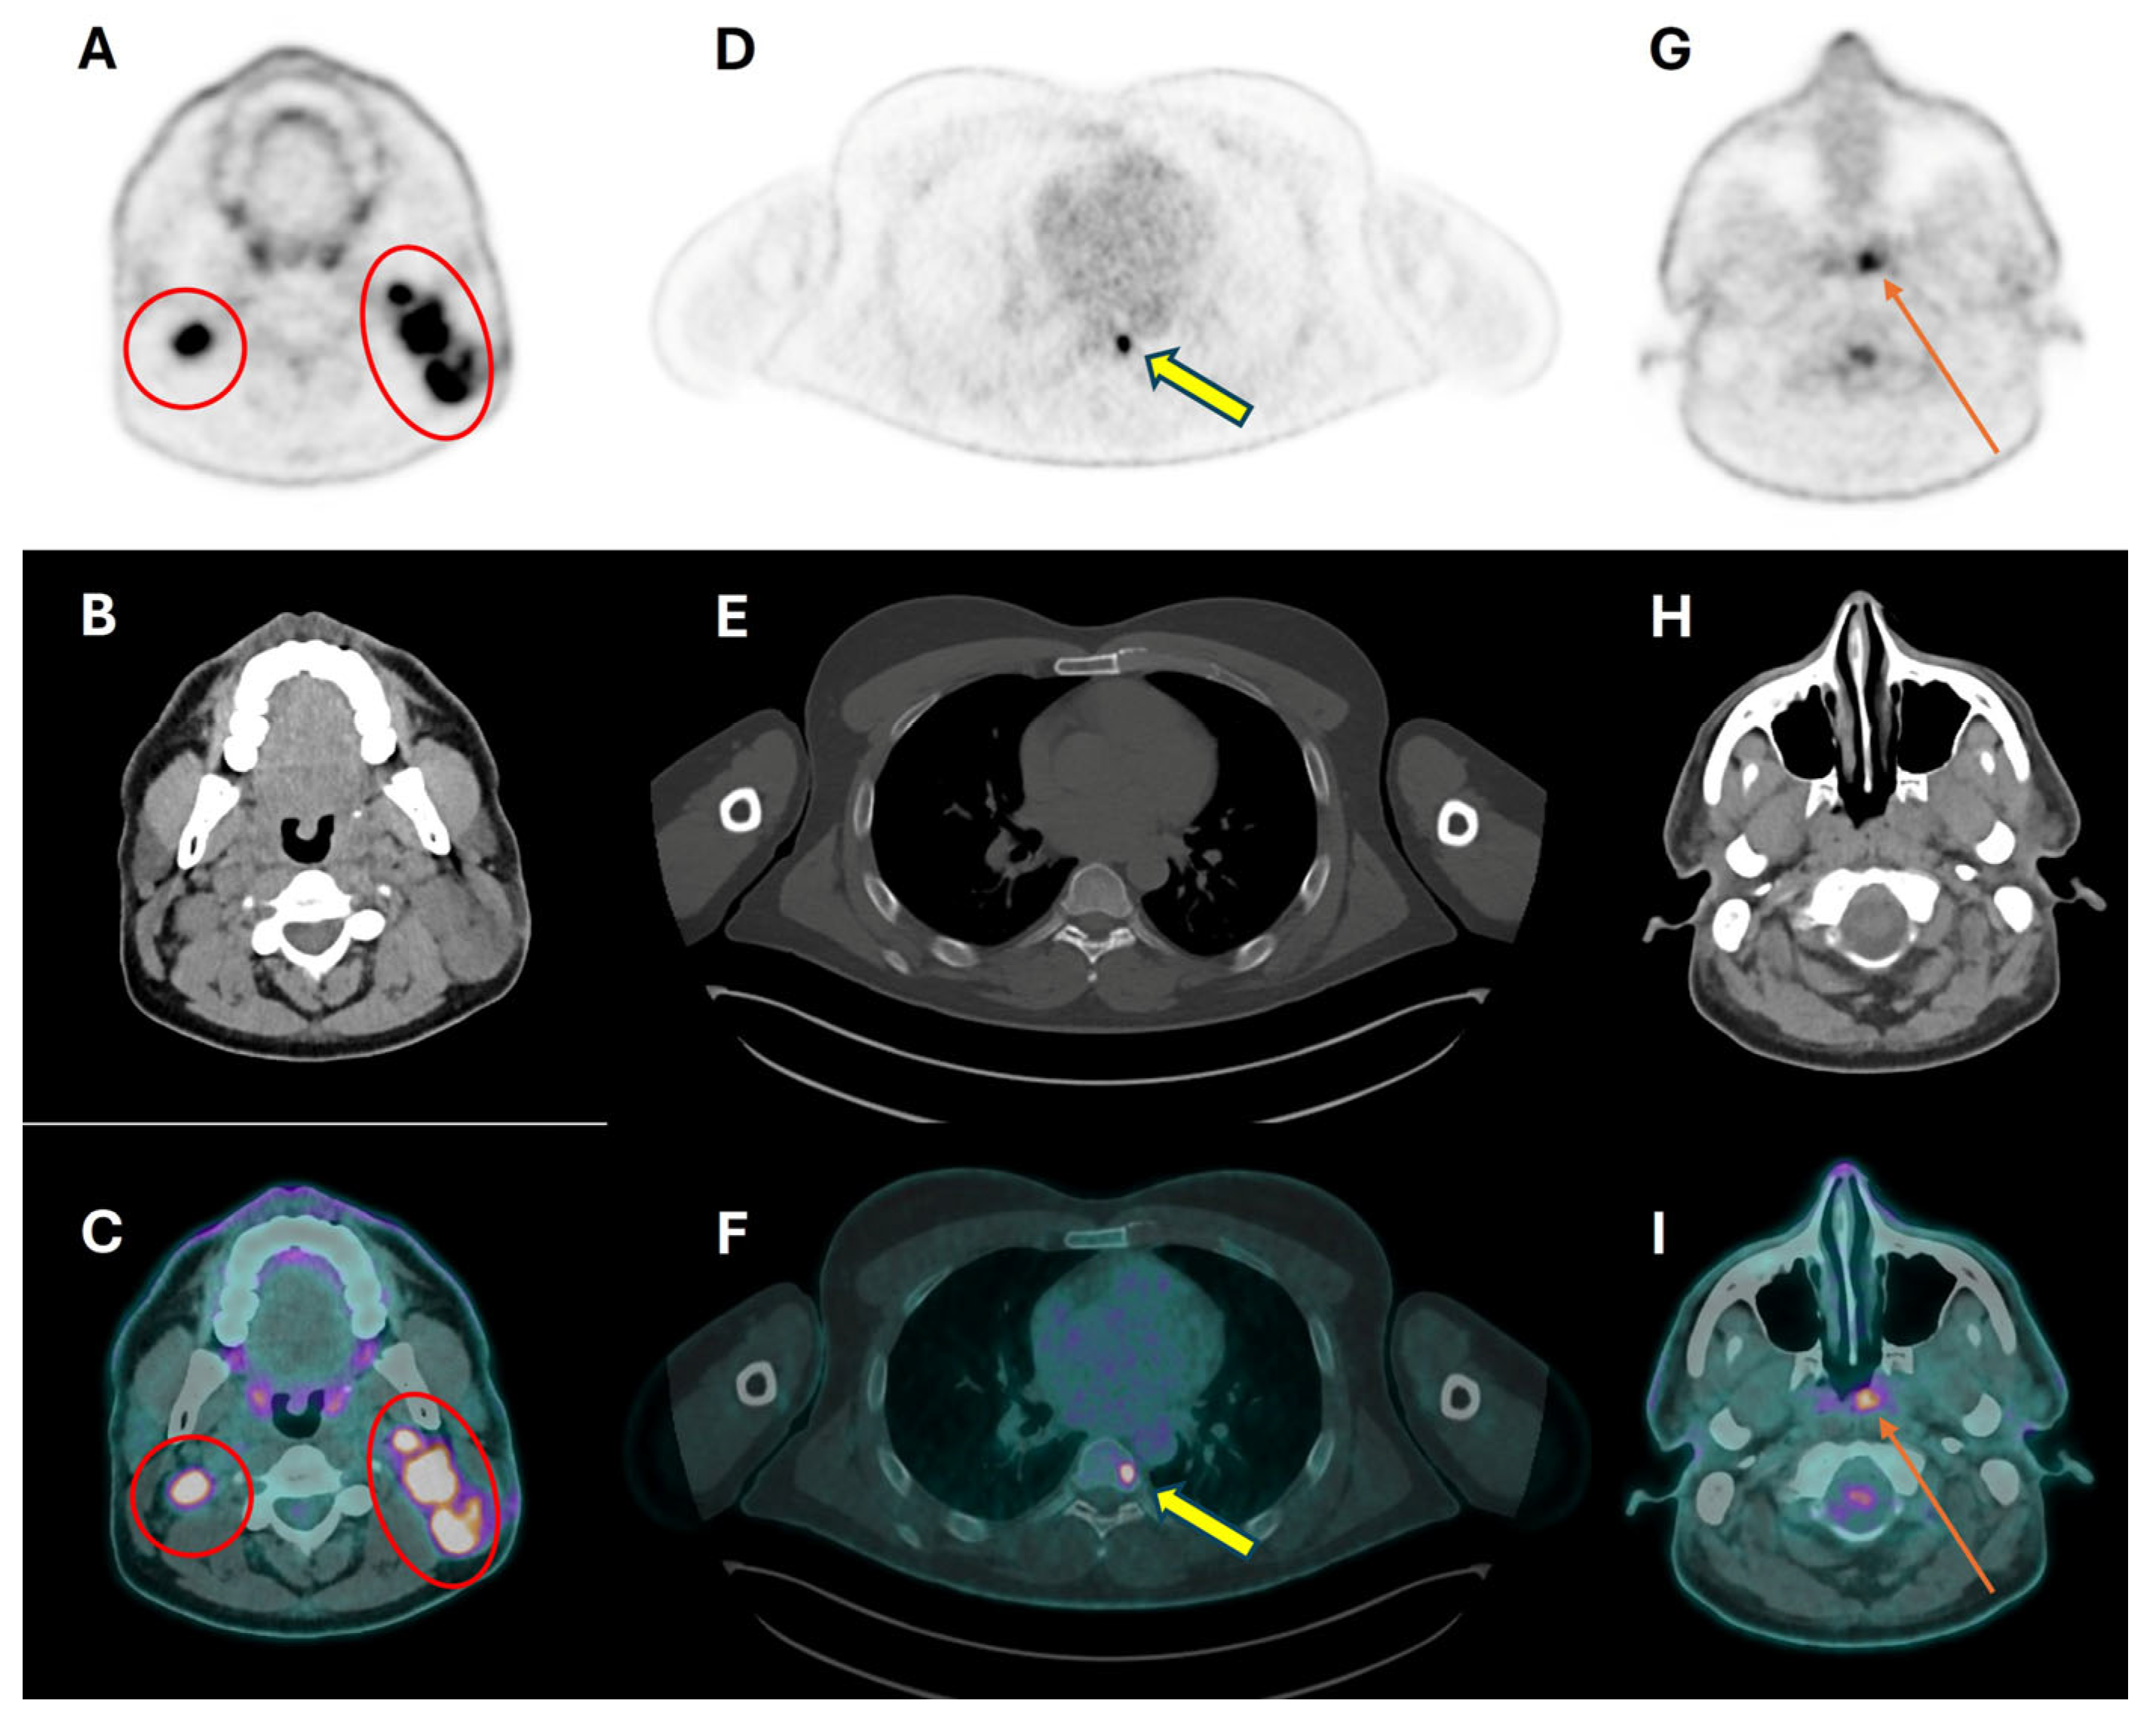

| Selection and delineation of GTV | - Detection of occult primary tumor (see text) - Tumor extension not defined on CT or MRI (see Figure 3) |